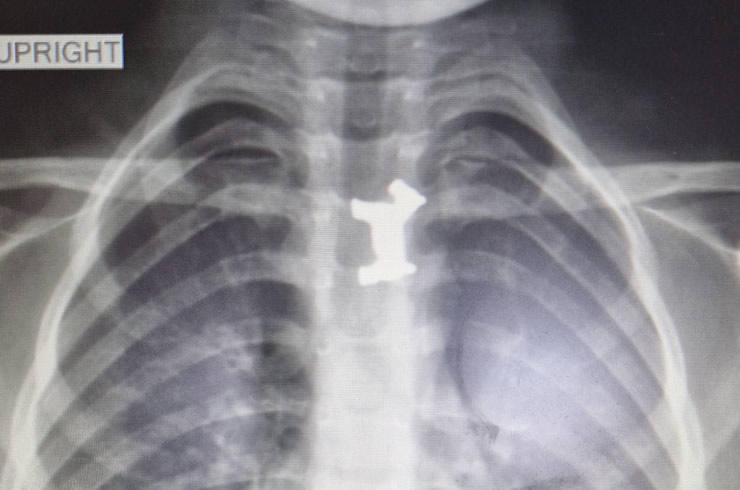

Το αγοράκι εμφάνισε σιελόρροια, οι γονείς του το πήγαν στο Γενικό Νοσοκομείο Σερρών όπου εξετάστηκε από τους γιατρούς, η ακτινογραφία έδειξε ότι είχε καταπιεί και είχε σφηνώσει στον οισοφάγο του ένα μεταλλικό παιχνίδι. Αποφασίστηκε η διακομιδή του στο Ιπποκράτειο Νοσοκομείο Θεσσαλονίκης.

Εκεί οι παιδίατροι ακολούθησαν την προβλεπόμενη διαδικασία σε αντίστοιχες περιπτώσεις, το πρωί υποβλήθηκε σε χειρουργική επέμβαση και οι γιατροί κατάφεραν να αφαιρέσουν με επιτυχία το μεταλλικό σκυλάκι από τον οισοφάγο του παιδιού. Ο μικρός νοσηλεύεται προληπτικά και είναι καλά στην υγεία του. Το σκυλάκι προερχόταν από γνωστό επιτραπέζιο παιχνίδι.